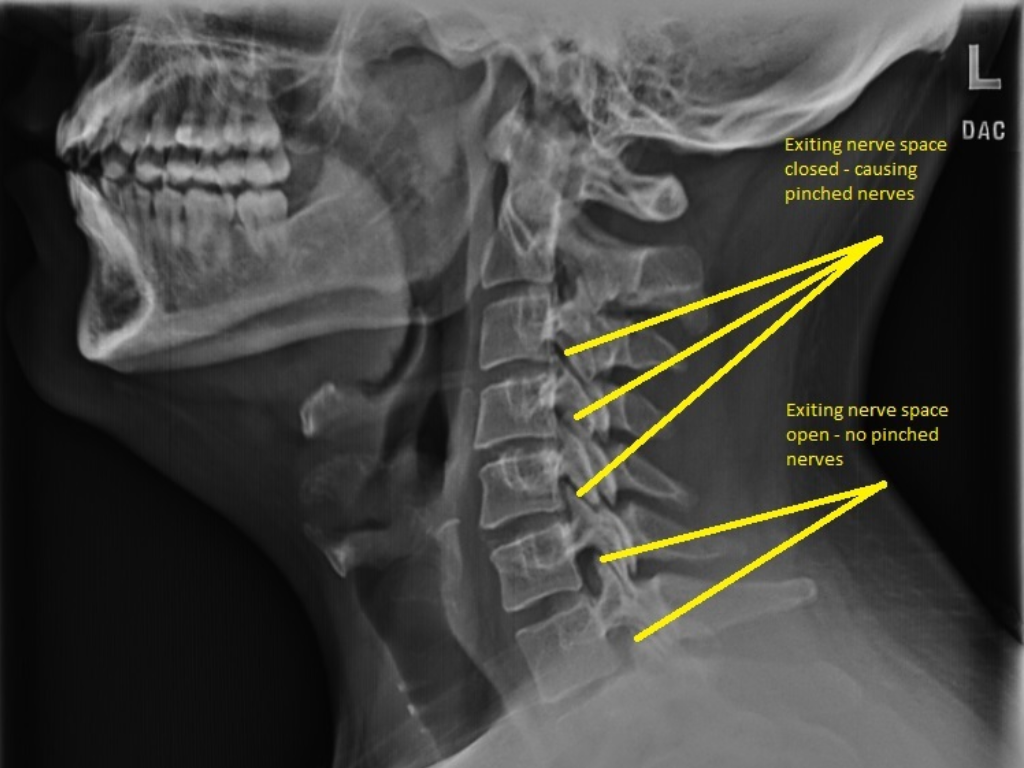

Dr. Asher uses state-of-the-art X-ray technology to asses each patient’s underlying skeletal structures. If necessary for your condition, we may suggest X-rays. These X-rays are essential for creating the most effective treatment plan and identifying any significant spinal conditions. Reviewing your X-rays up close can provide valuable insight, helping you gain a better understanding of your condition and available treatment options.